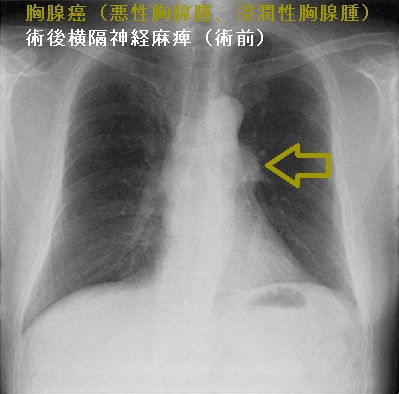

胸腺癌(悪性胸腺腫、浸潤性胸腺腫)は前胸部から肺門部まで浸潤し、横隔神経自体にも浸潤するため、摘出手術で横隔神経を損傷する可能性が高い(術後横隔神経麻痺)。術後横隔神経麻痺では、術後から息が深く吸えなくなります。内肋間筋・補助呼吸筋と代償性の呼吸数増加で補える場合が多いが、重症例は胸腔鏡下横隔膜縫縮術の適応。

術後横隔神経麻痺は、特に浸潤性の強い甲状腺癌、前縦隔に浸潤する甲状腺癌(甲状腺未分化癌 甲状腺原発扁平上皮癌 など)の切除手術後にも起こります。